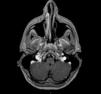

The West Nile virus (WNV) is an arbovirus than can infect human beings and cause severe neuroinvasive disease. Taking the outbreak that occurred in Spain in 2020 as a reference, this article reviews the clinical and imaging findings for neuroinvasive disease due to WNV. We collected demographic, clinical, laboratory, and imaging (CT and MRI) variables for 30 patients with WNV infection diagnosed at our center. The main clinical findings were fever, headache, and altered levels of consciousness. Neuroimaging studies, especially MRI, are very useful in the diagnosis and follow-up of these patients. The most common imaging findings were foci of increased signal intensity in the thalamus and brainstem in T2-weighted sequences; we illustrate these findings in cases from our hospital.